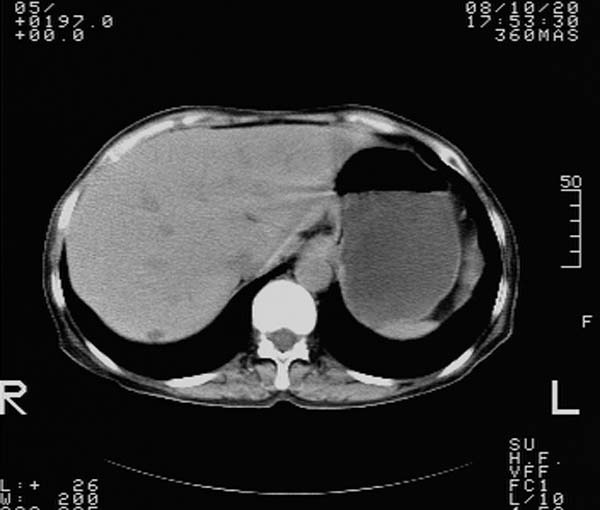

f,67y。反复右上腹痛。余无异常。

前五幅未服造影剂。后面图像有上传重复的。请战友们发表意见。

胆囊结石、胆囊癌伴邻近脏器受侵,不除外黄色肉芽肿性胆囊炎,建议增强扫描。肝多发囊性占位性病变,囊肿或囊性转移。

胆囊结石、胆囊癌伴邻近脏器受侵,肝转移可能

胆囊内结石,胆囊壁不规则增厚,胆囊胃窦区解剖结构欠清晰,楼主提示为少见病,考虑bouveret综合征?黄色肉芽肿性胆囊炎?肝内多发低密度占位,建议增强或b超